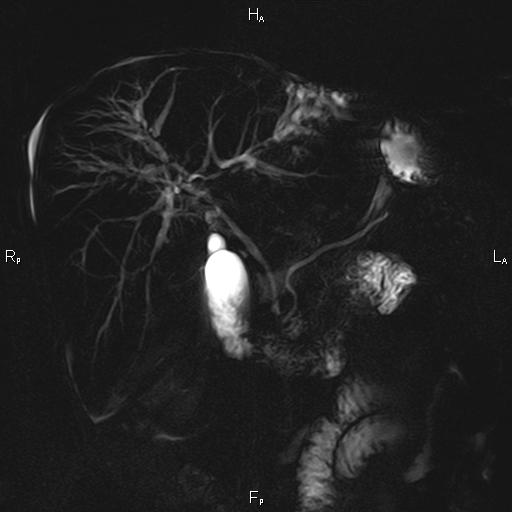

ΚΛΙΝΙΚΑ ΣΤΟΙΧΕΙΑ – ΙΣΤΟΡΙΚΟ

Ανώδυνος ίκτερος και παθολογικά ηπατικά ένζυμα. Ιστορικό πιθανής σκληρυντικής χολαγγειίτιδας

ΑΠΕΙΚΟΝΙΣΤΙΚΟΣ ΕΛΕΓΧΟΣ

Μαγνητική τομογραφία.

Η διάγνωση της βασίζεται στα τυπικά χολαγγειογραφικά ευρήματα κατά την μαγνητική και την ενδοσκοπική παλίνδρομη χολαγγειοπαγκρεατογραφία (MRCP-ERCP).

Οι αρχικές εξετάσεις εκλογής, όσον αφορά τον απεικονιστικό κυρίως έλεγχο, σε ασθενή προσερχόμενο στο Νοσοκομείο με αποφρακτικό ίκτερο, είναι το υπερηχογράφημα και η αξονική τομογραφία. Οι εξετάσεις αυτές έχουν αποδειχθεί ικανές να προσδώσουν έμμεσα και άμεσα στοιχεία για τη διάγνωση του χολαγγειοκαρκινώματος, όμως κυρίαρχη εξέταση για την διάγνωση του χολαγγειοκαρκινώματος είναι η μαγνητική τομογραφία (MRI, MRCP, MRA).